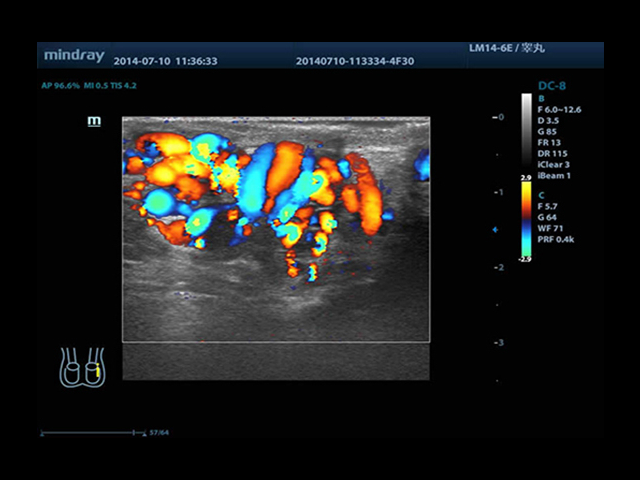

Mindray DC-8 Exp оснащен новым поколением датчиков с увеличенным количеством элементов и инновационной технологией "3T". Это позволяет достичь высокой детализации и качества изображения. Благодаря новейшей технологии iFlow, можно визуализировать даже самые мелкие сосуды и кровеносные пути.

Сверхширокополосная нелинейная обработка изображений снижает визуальные шумы на 30% по сравнению с другими системами. Технология iClear позволяет устранить зернистость изображения, а iBeam (технология пространственного компаундинга) обеспечивает высокое качество сканирования органов и тканей под различными углами.

• Высокочастотный линейный датчик 38 мм Mindray l14-6NE